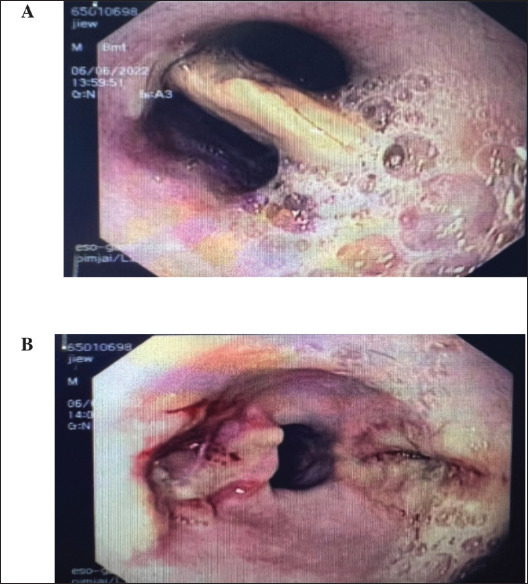

目的:本研究旨在识别、分类和比较狗的胃肠道异物,特别关注那些引起阻塞的异物。该研究还试图区分食道和胃中的异物,包括骨头、塑料袋、水果种子、石头和金属丝等物质的类型。方法:对261只犬(公151只,母110只)的食管或胃异物(n = 111)进行回顾性研究。样本包括188只小型犬(24公斤)。结果:胃异物(57.47%)高于食管异物(42.53%)。食道病例以小型犬为主(92.79%),中型犬占很小比例(7.21%)。胃病例中,小型犬数量较多(56.67%),中型犬(22.00%)和大型犬(21.33%)比例显著。小型犬更容易在食道中发现异物,而大型犬(中型和大型犬)更容易在胃中发现异物(p < 0.001)。食道和胃之间出现了明显的物质形态。值得注意的是,食管(61.26%)和干狗零食(23.42%)的发生率高于胃(分别为2.67%和0.00%)。相反,胃中织物(20.00%比1.80%)、植物材料(18.67%比4.50%)、金属物体(18.00%比8.11%)、岩石(12.67%比0.9%)、橡胶材料(10.67%比0.00%)、塑料材料(6.67%比0.00%)和毛球(2.67%比0.00%)的发生率分别较高。时间分析显示,在食管内,28.83%的病例在24 h内取出异物,56.76%的病例在2-7天内取出,14.41%的病例在7天以上取出异物。对于胃内异物,23.33%在24小时内取出,30.00%在2 ~ 7天内取出,22.00%在7天以上取出,24.67%时间不详。其中,食管异物111例,胃异物150例。主要采用内镜方法清除异物,4例(3.60%)食管和8例(5.30%)胃需要手术,包括不可破碎的骨头和橡皮鸭等耐药物品。在完全随访的犬中,手术切除食管异物的死亡率(3/4,75.00%)高于内镜切除(3/56,5.36%)(p < 0.002),而手术或内镜切除胃异物的犬无死亡(p = 0.149)。结论:食管异物主要由骨头和狗干零食组成,胃异物多由织物、植物材料和金属物体组成。这些组成上的差异突出了针对具体地点的管理策略的必要性。

Results: The study's findings indicate a higher prevalence of gastric foreign bodies (57.47%) compared to esophageal foreign bodies (42.53%). Small breeds dominated esophageal cases (92.79%), with only a small percentage being medium breeds (7.21%). In contrast, gastric cases included a high number of small breeds (56.67%), as well as significant percentages of medium (22.00%) and large breeds (21.33%). Small-breed dogs were more likely to have foreign bodies in the esophagus, while larger dogs (medium and large breeds) were more likely to have them in the stomach (p < 0.001). Distinct material patterns emerged between the esophagus and stomach. Notably, the esophagus showed a higher incidence of bones (61.26%) and dried dog snacks (23.42%) compared to the stomach (2.67% and 0.00%, respectively). Conversely, the stomach exhibited a higher incidence of fabrics (20.00% vs. 1.80%), plant materials (18.67% vs. 4.50%), metallic objects (18.00% vs. 8.11%), rocks (12.67% vs. 0.9%), rubber materials (10.67% vs. 0.00%), plastic materials (6.67% vs. 0.00%), and hairballs (2.67% vs. 0.00%), respectively. A temporal analysis revealed that within the esophagus, 28.83% of cases underwent foreign body removal within 24 h, 56.76% within 2-7 days, and 14.41% after more than 7 days. For foreign bodies within the stomach, removal occurred in 23.33% of cases within 24 h, 30.00% within 2 to 7 days, 22.00% after more than 7 days, and 24.67% at an unknown timing. A total of 111 cases involved foreign bodies lodged in the esophagus, and 150 cases involved items stuck in the stomach. Endoscopic methods were primarily employed to remove foreign bodies, with surgical intervention required for 4 (3.60%) esophageal and 8 (5.30%) gastric cases, including noncrushable bones and resistant items such as rubber ducks. In dogs with complete follow-up, surgical removal of esophageal foreign bodies had a higher mortality rate (3/4, 75.00%) compared with endoscopic removal (3/56, 5.36%) (p < 0.002), while no mortality was observed in dogs with gastric foreign bodies undergoing surgical or endoscopic removal (p = 0.149).

Conclusion: Esophageal foreign bodies were primarily composed of bones and dried dog snacks, while gastric foreign bodies more often contained fabrics, plant materials, and metallic objects. These composition differences highlight the need for site-specific management strategies.